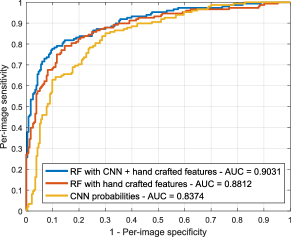

Our combined approach shows an analogous behavior when evaluating on e-ophtha for DR screening, as illustrated in Figure 12. Our combined approach retrieved a significantly higher AUC value (0.9031) than the one reported by the CNN (AUC = 0.8374, ) and the RF classifier trained with hand crafted features (AUC = 0.8812). Hand crafted features perform better than the CNN for screening in this data set, although the difference is not statistically significant according to the Mann-Whitney test.